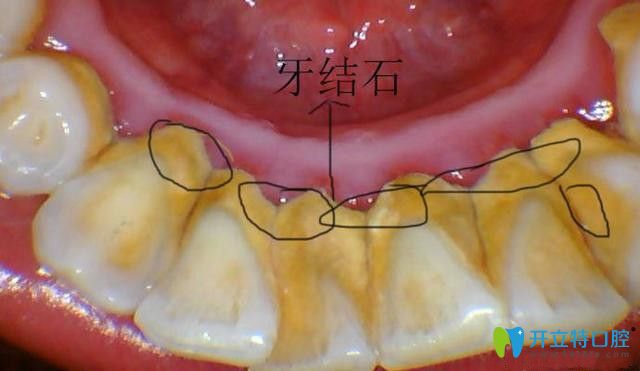

所以超聲波潔牙是可以去除牙斑菌、牙結(jié)石,又要的預(yù)防牙周炎、牙齦炎等口腔疾病,是很好的牙齒護(hù)理方法,對(duì)牙齒無害。

超聲波去牙結(jié)石